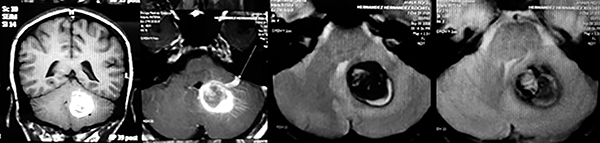

Paciente femenino de 29 años de edad con historial de cefalea crónica que presenta súbitamente disdiadococinesia y dismetría izquierda.

El estudio de RMN presenta una lesión bien circunscrita en hemisferio cerebeloso izquierdo con periferia de predominio hiperintenso en T1 y T2, y centro hipointenso, edema perilesional mínimo, así como una imagen de un vaso venoso alimentador que recorre hacia el ángulo pontocerebeloso izquierdo.

Se realizó una craniectomía suboccipital paramedial derecha, así como un abordaje transcortical en el hemisferio cerebeloso izquierdo llegando a la región perilesional de aspecto amarillento, posteriormente se observa una lesión oscuro-verdoso de contenido hemático antiguo, retirando la cápsula y su contenido en la totalidad.

La evolución clínica de la paciente fue satisfactoria solo preservando la dismetría como secuela.

El resultado histopatológico fue consistente en angioma cavernoso.

El estudio de control de RMN se observa la brecha quirúrgica y ausencia de lesión (figs. 1, 2 y 3).

Figura 1:

Lesión cerebelosa izquierda ponderaciones en T1 y T2, la flecha señala vaso nutricio hacia el ángulo pontocerebeloso izquierdo, se puede observar el centro de intensidad heterogénea con contenido quístico multiloculado y edema perilesional leve.

Figura 2:

Cortes axiales en ponderación T1, cambios postquirúrgicos.